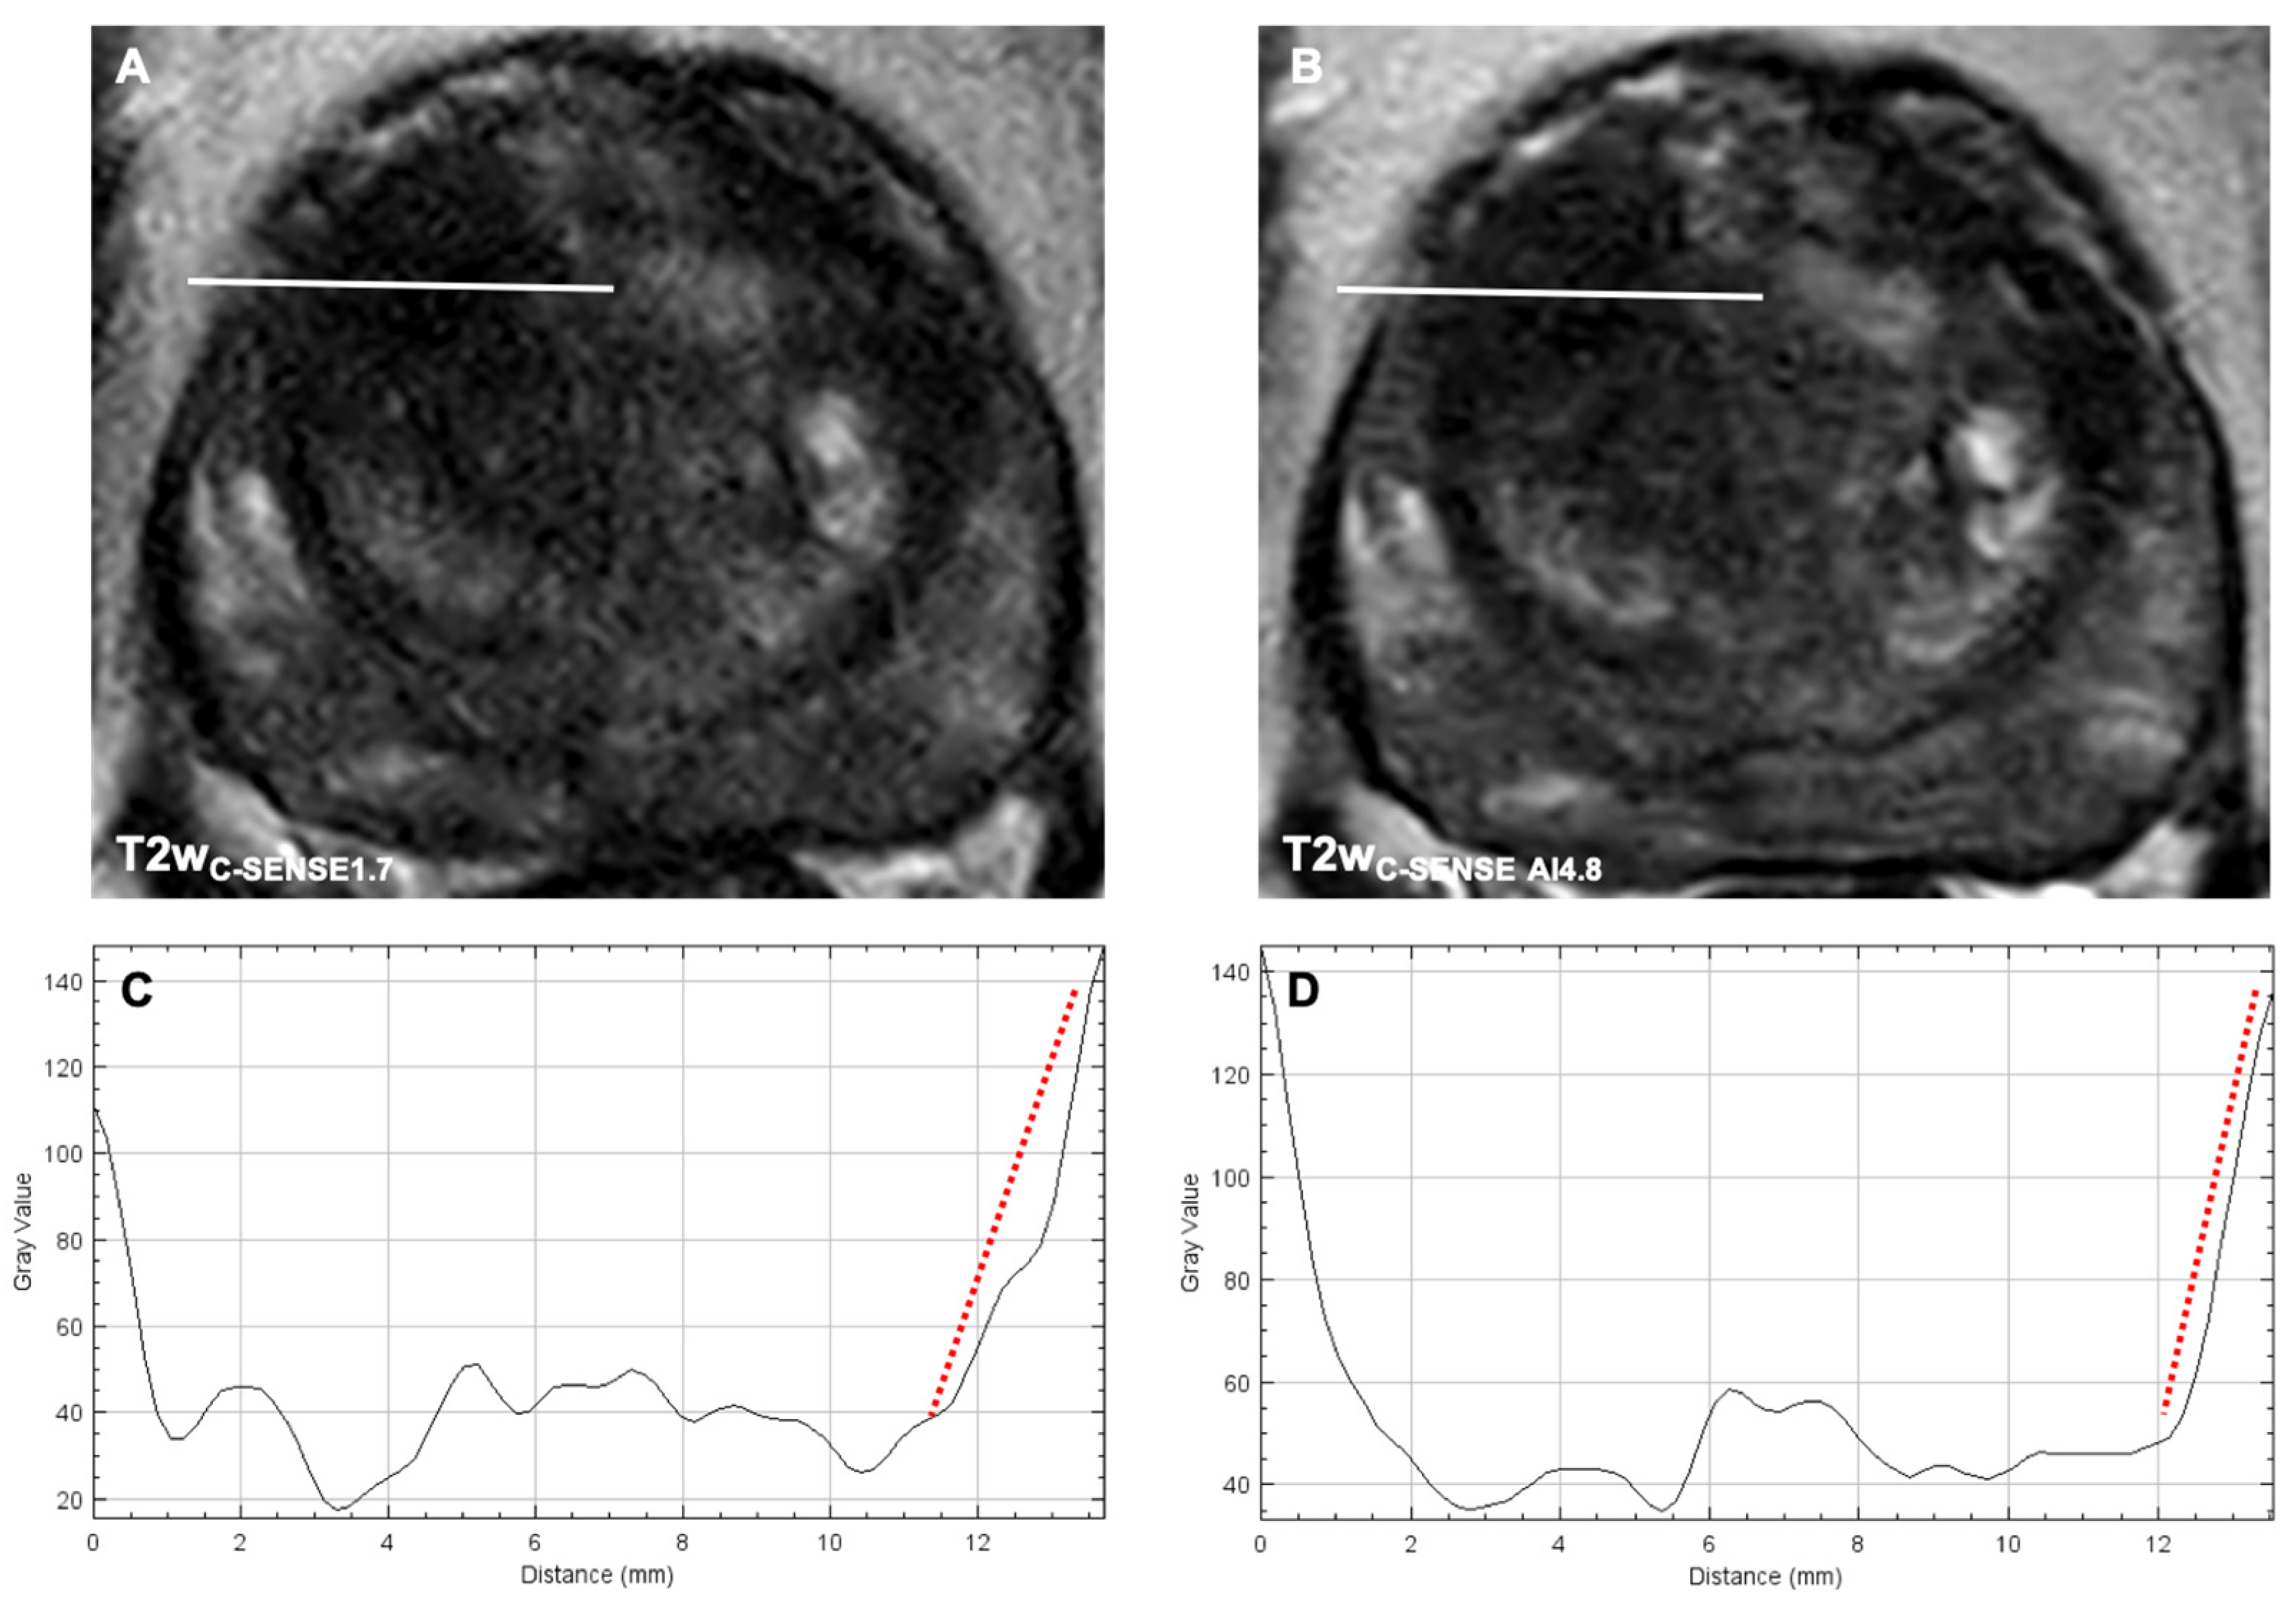

3.3.3. Image Sharpness